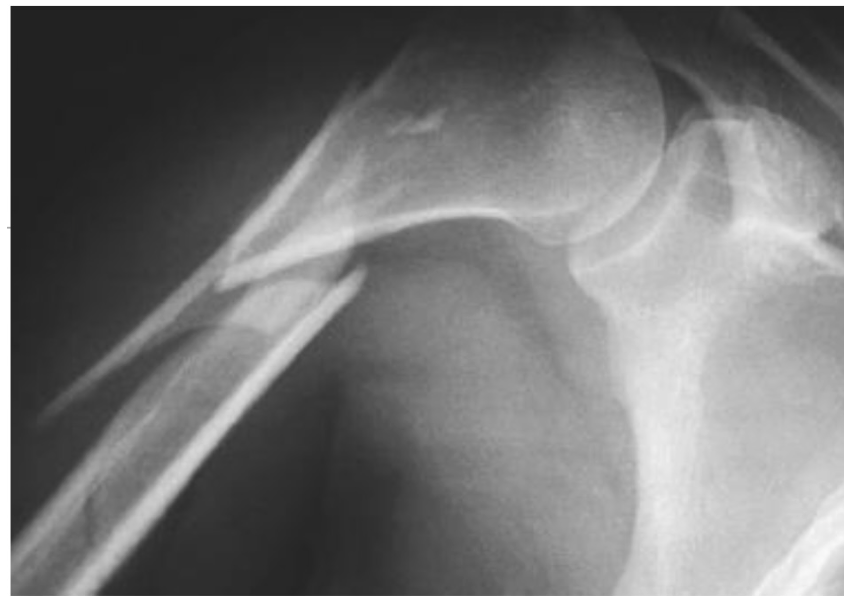

SUPRACONDYLAIRE HUMERUSFRACTUUR (KINDEREN)

Q: Meest voorkomende elleboogfractuur bij kinderen?

Q: Mechanisme?

Q: Classificatie?

Q: Belangrijke complicatie?

Q: Behandeling?

Ja, supracondylair.

Val op gestrekte arm.

Gartland (I–III)

Zenuwschade (n. medianus, ulnaris, radialis)

Vaatletsel

Repositie (hyperflexie)

Zo nodig K-draden